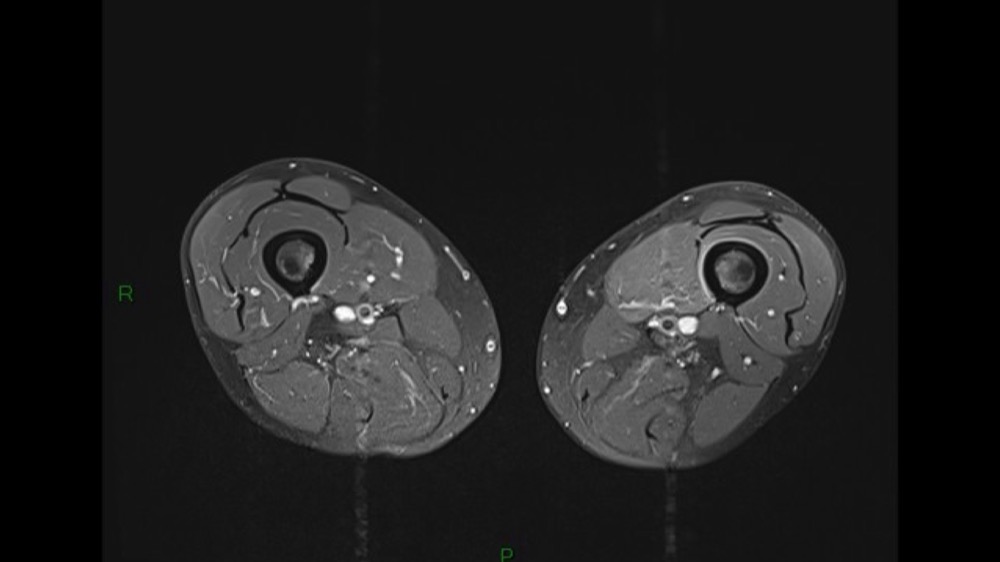

Lombo-cruralgie subaiguë trompeuse

Pascalie Jallerat 22/06/2020